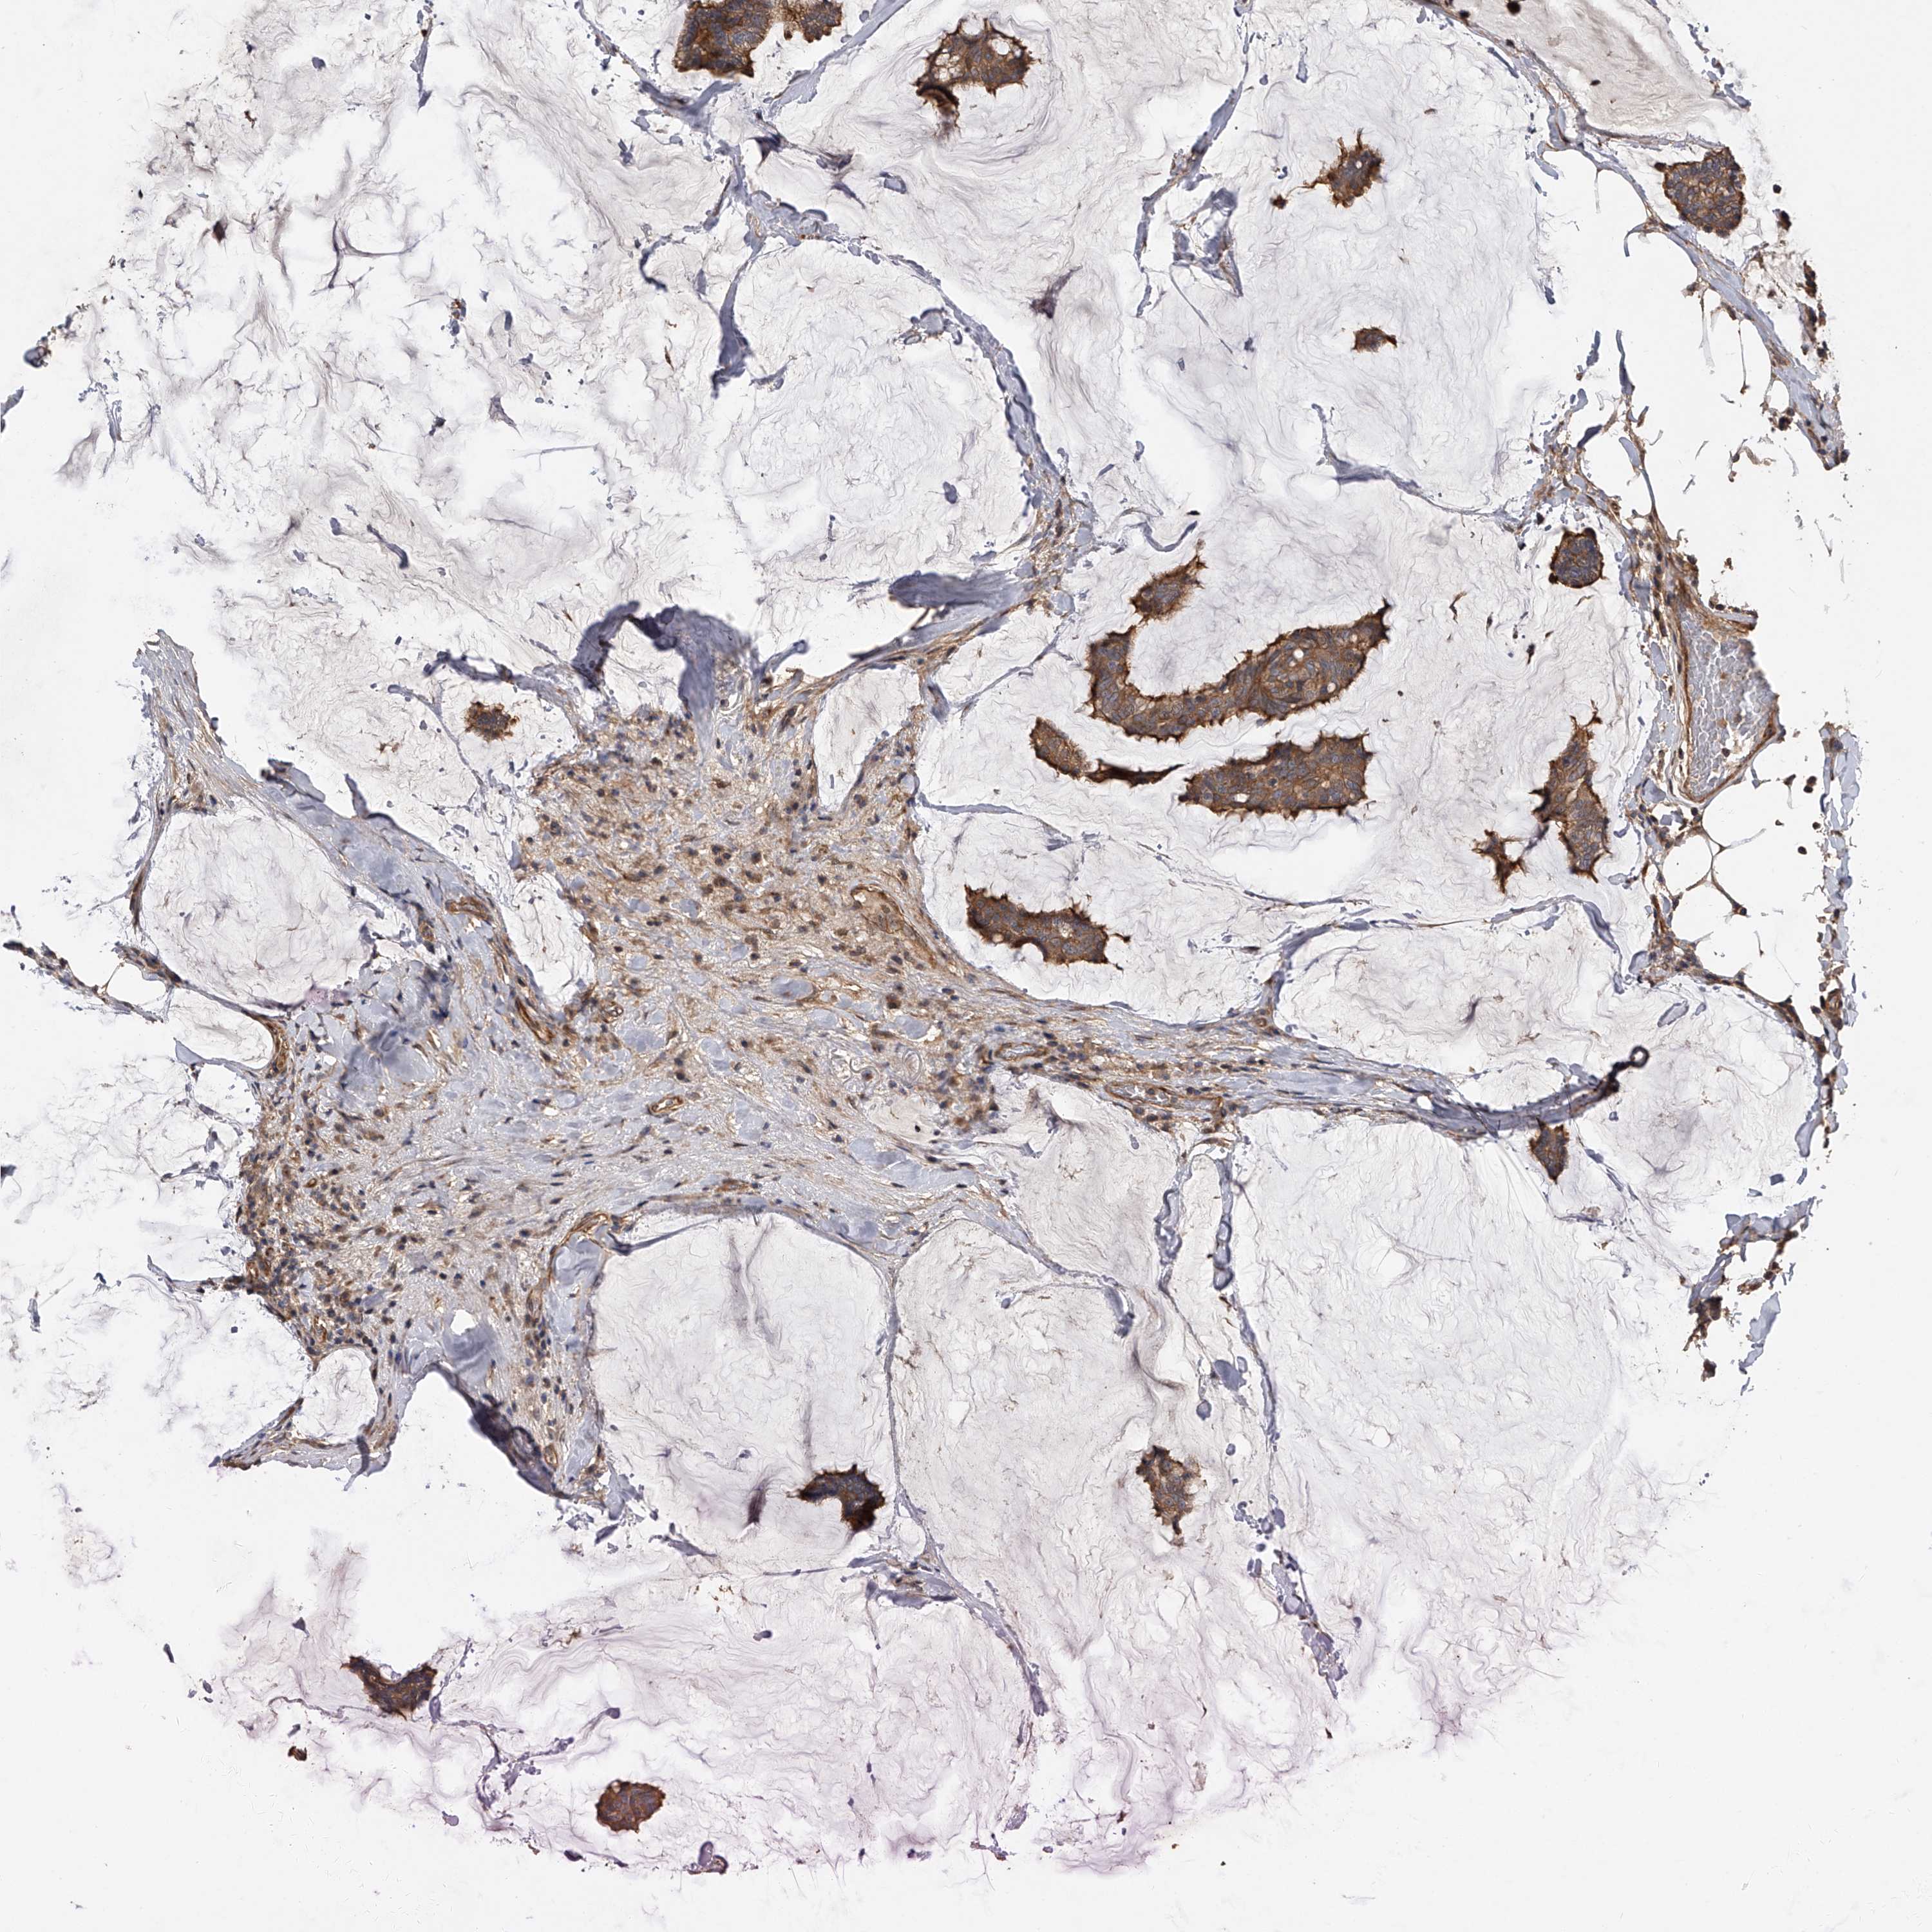

CANCER BREAST CANCER Show tissue menu

BRCA TCGA BRCA VALIDATION PROTEIN EXPRESSION